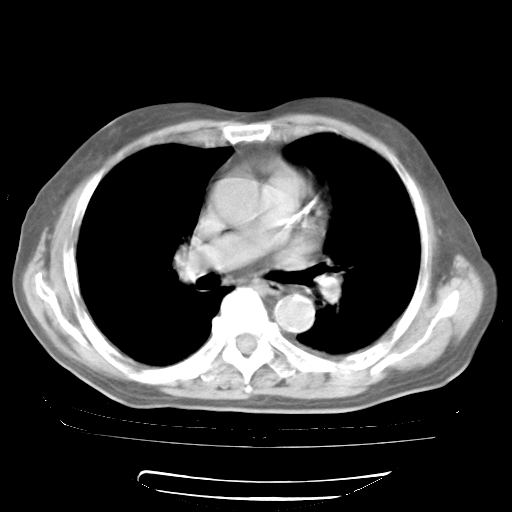

4月28日肺部CT——再次出现类似去年5月9日——透光度降低,“间质性”改变。

4月28日肺部CT——再次出现类似去年5月9日——磨玻璃样、间有“粟粒样”改变。

4月28日肺部CT

个人阅读4.14日肺部CT平扫:纵隔窗无异常,但肺窗示:双下肺内、后基底段有片絮状侵润影,部位以后基底段为著,以间质改变为主,呈急性肺泡炎征像,和首次住院影像学有相似之处。仅是个人读片,明日请相关专家再读片哈。其它建议同上。

1、108#的是4月14日的胸部CT(发此贴时还没看着28日的CT)。14日的胸部CT其实已经出现改变(如108#所述),个人认为28日的胸部CT除纵膈窗疑似有双侧胸膜增厚或少量胸积液(可行胸部B超明确)外,与4月14日对照病变有所加重;2、已经给予“异烟肼、利福平、乙胺丁醇”抗痨治疗?如果是,甲强龙80mg可缓慢减量;如果环磷酰胺已停用,暂不使用;3、中性粒细胞92%,明显升高,目前体温情况?注意合并细菌感染可能,使用左氧氟沙星情况下,是否联用B-内酰胺类抗菌药物?另外是查免疫全套非风湿全套。

今请临免主任会诊后认为:4月14日胸部CT已有双下肺间质性改变。患者病情复发多系激素减量过快不正规所致。目前甲强龙80mg/日,一周后酌情开始减量,不易过快。环磷酰胺若已停用,暂不使用。他同意目前抗菌药物使用,但应考虑是否加用B-内酰胺类抗菌药物(中性细胞明显增高);2、结核复发目前依据不足;3、若免疫全套各项指标正常,考虑多系特发性肺间质炎可能大。4、加强支持,并注意保护胃黏膜。